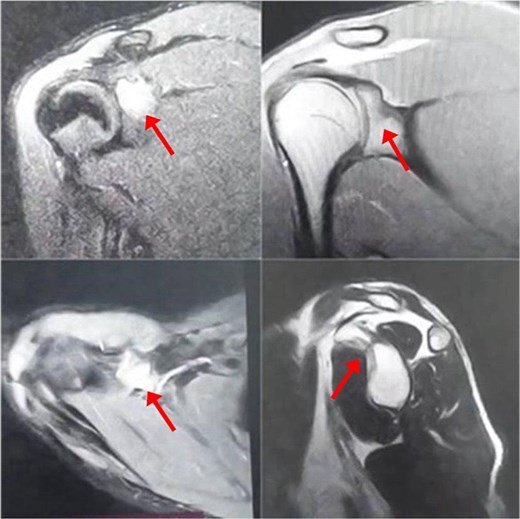

A 17-year-old male presented with left shoulder pain and limited range of motion for 2 months, with no history of trauma or prior medical or surgical issues. On examination, there was tenderness localized to the coracoid process. Initial laboratory tests, including complete blood count (CBC), C-reactive protein (CRP), and erythrocyte sedimentation rate (ESR), all normal. Conservative management with rest and non-steroidal anti-inflammatory drugs (NSAIDs) was initiated, but there's no improvement. Initially, imaging with an X-ray revealed a suspicious lesion at the base of the coracoid process (Fig. 1), prompting further evaluation with magnetic resonance imaging (MRI) without contrast, which confirmed the lesion in the base of the coracoid with surrounding fluid and edema extending to the coracoid-humeral space (Fig. 2).

MRI without contrast of the left shoulder show a cortical and subcortical bony defect at the glenoid basecoracoid junction with hyperintense lesion measuring 8 × 7 mm (indicated by arrow), also intense bone marrow edema at the coracoid processes and the glenoid base-coracoid with surrounding fluid and edema extending to the coracoid-humeral space was seen.